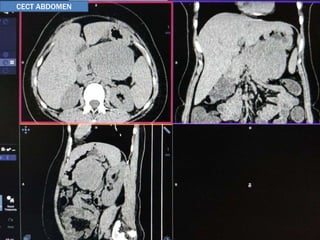

 A female patient of 30yrs of age

 Presented with complaints of vague abdominal discomfort for

last 3 months

 No other significant clinical or past history

 Clinical examination: WNL

CASE 1

USG ABDOMEN

CECT ABDOMEN